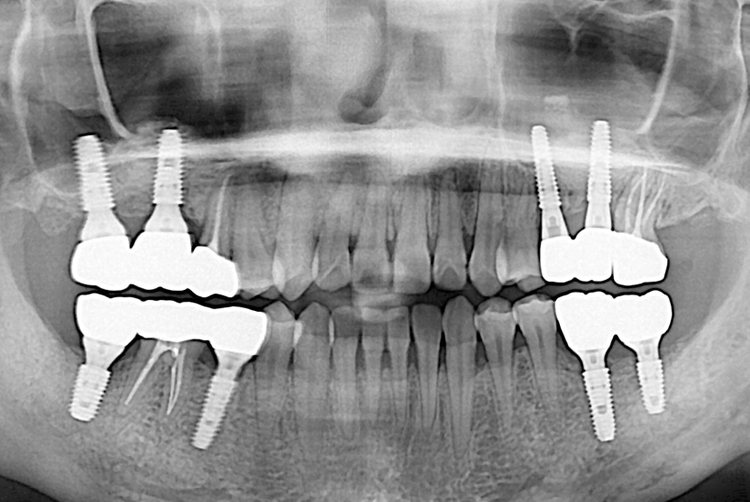

[임플란트] 임플란트

7cf8ead315147d1dd75f24443708e3e4.jpg

치료전 : 2018-01-10

세종치과는 많은 환자와 다양한 케이스를 바탕으로 항상 편안한 임플란트 수술을 제공하고자 노력하고,

오래동안 튼튼히 쓸 수 있는 임플란트 수술을 가장 큰 목표로 삼고 있습니다